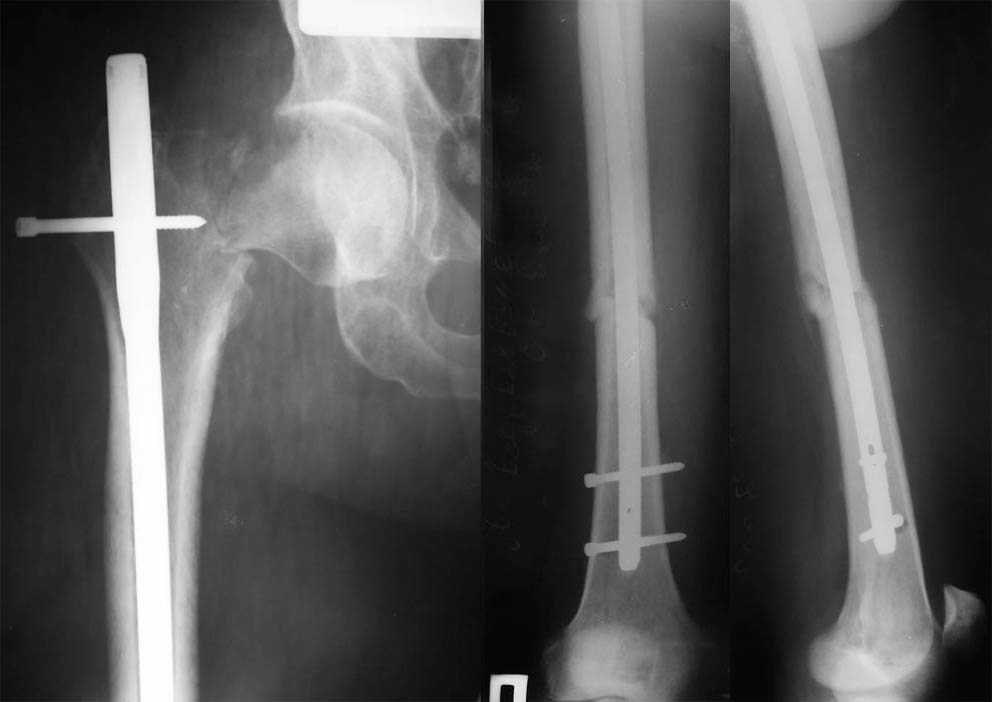

This is very bad situation. To miss fracture subcapital like this is unforgivable. Now the fracture of the femoral shaft isn't healed with malreduction component and fracture of the subcapital femur (doesn't matter what grade) without any chance for healing. More of them, therк is very high chanse to AVN of the femoral head. At the moment nothing can be done exept change of the intramedullary nail in femoral shaft

with femoral neck fixation after open reduction . I mean PF Aesculap nail or TAN Smith & Nerphuy). After that waiting with hoope to union of the femoral shaft fracture and, depending on condition of the femoral head, in the life - suprise, or go to THR noncemented if the head will be dead. Any way this young man is invalid. Good luck !

I was sure that you can read in english.At the moment nothing can be done exept change of the intramedullary nail in femoral shaft.Nail with femoral neck fixation after open reduction. This may be PF Aesculap nail or TAN Smith & Nerphuy

А открытая репозиция шейки окончательно не лишит кровоснабжения головку? Не говоря о технической сложности вальгизации проксимального отдела бедра при фиксации гвоздем.

Наверно, вариант с вальгизирующей остеотомией с фиксацией blade plate или DHS более щадящий. А диафиз можно рефиксировать ретроградно. Или про эндопротезирование с очень длинной ножкой подумать.